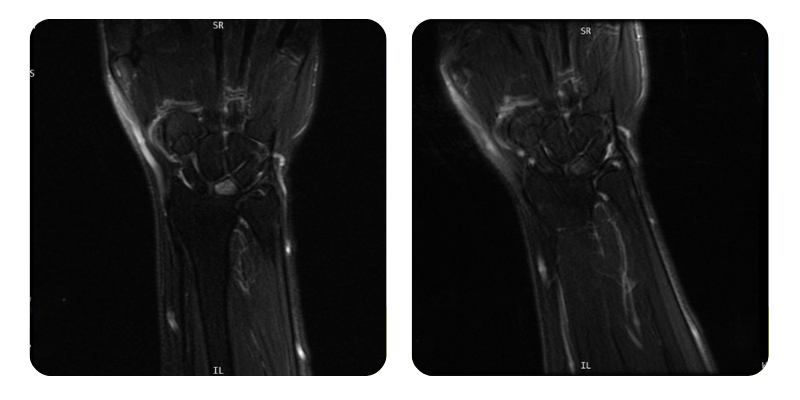

Înainte

După

B.A.A., 54 de ani - Osteonecroză avasculară semilunar stânga

Rezultate: RMN mână.

Diagnostic: Osteonecroză avasculară semilunar stânga, HTA, Hipotiroidism.

Evoluție: După finalizarea celor 20 de ședințe de terapie hiperbară, pacienta prezintă o remisie de aproximativ 80%, cu dispariția completă a durerilor la nivelul mâinii stângi. Nu se mai constată limitări funcționale, iar pacienta și-a reluat activitatea obișnuită fără disconfort.